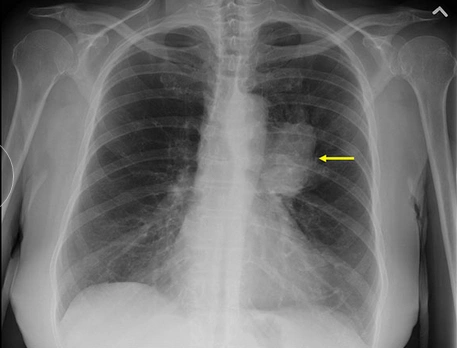

【读片】肺癌? [病例帖]

【原创】肺癌影像集锦

肺癌肉瘤x线-ct病例图片影像诊断分析!

【读片】右肺上叶中央型肺癌,前纵隔囊性密度影是什么结构 [病例帖]